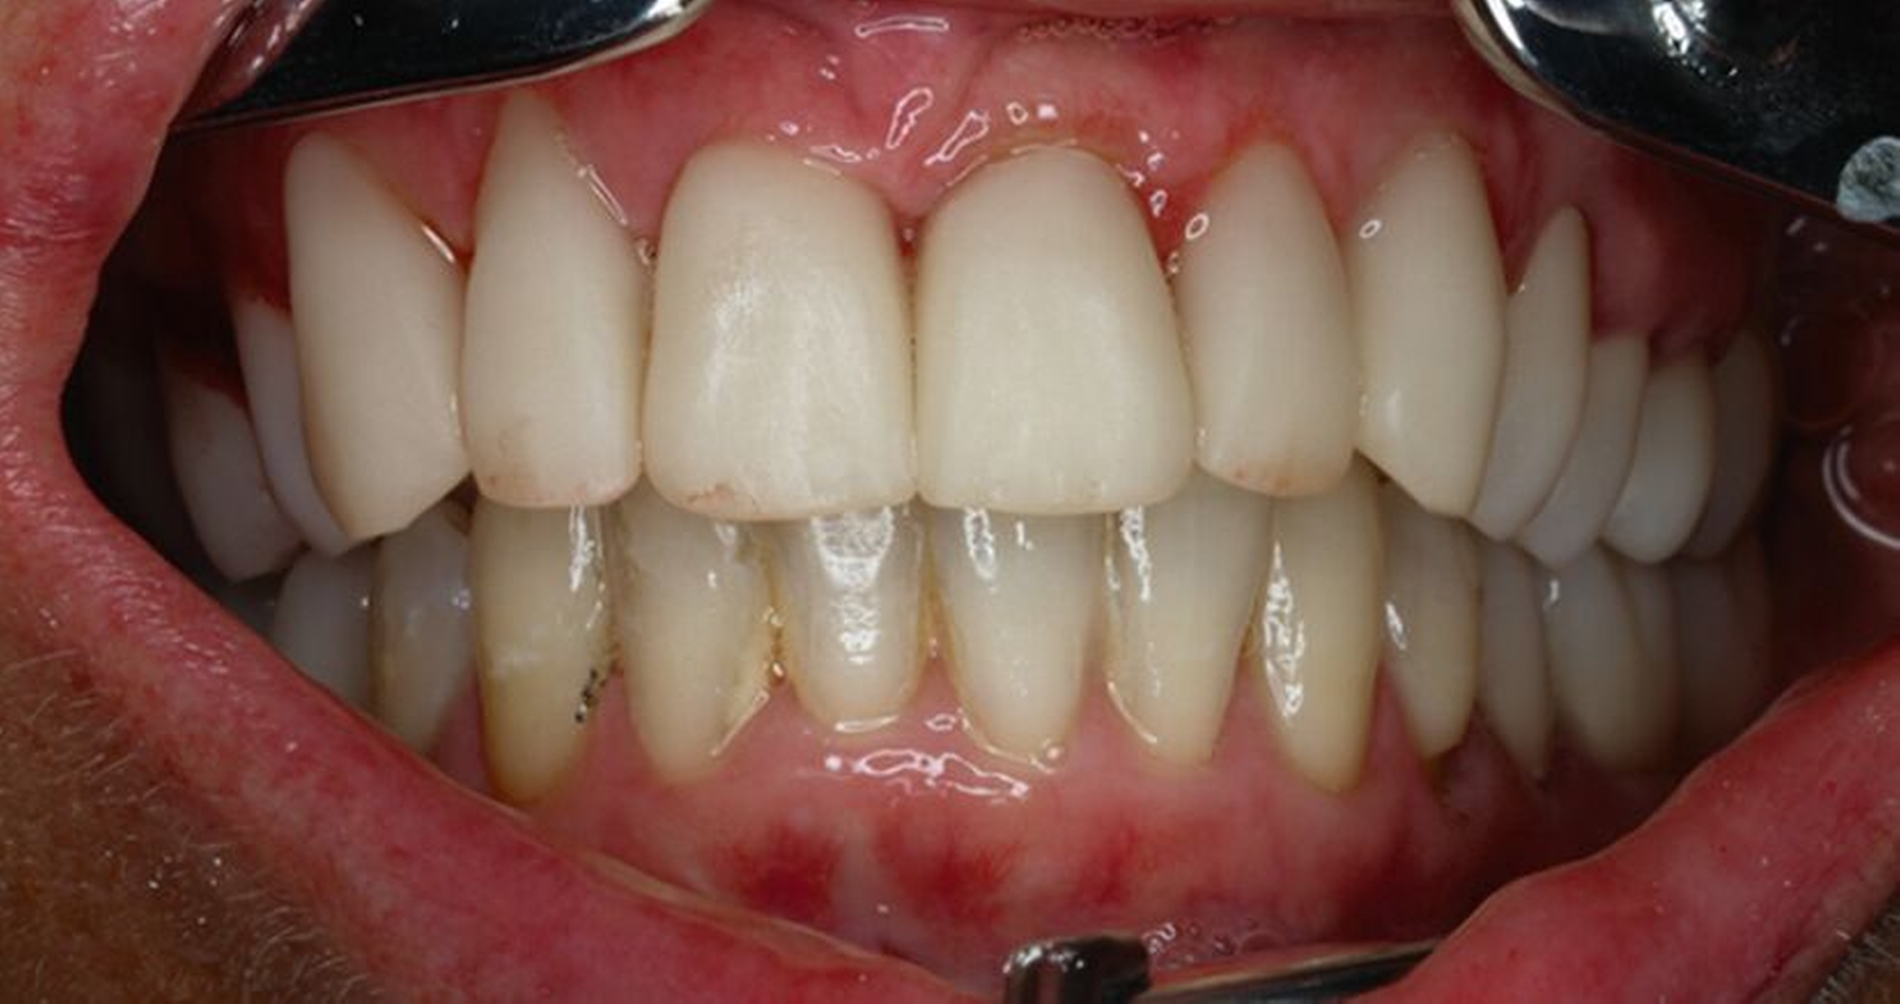

Die anschließenden Verlaufskontrollen zeigten klinisch stabile Verhältnisse. Der prothetische Behandlungsaufwand betrug etwa acht Monate inklusive Planung, Begutachtung, Durchführung und Inkorporation des Zahnersatzes. In den Folgeterminen wurde der Patientin noch eine Aufbissschiene für den Unterkiefer eingegliedert, um Schäden durch etwaigen Schlafbruxismus vorzubeugen [Macedo et al., 2007]. Für die Nachsorge empfiehlt sich ein halbjährliches Kontrollintervall. Die erfolgte Okklusionskorrektur im Seitenzahnbereich wird in Abbildung 11 deutlich.